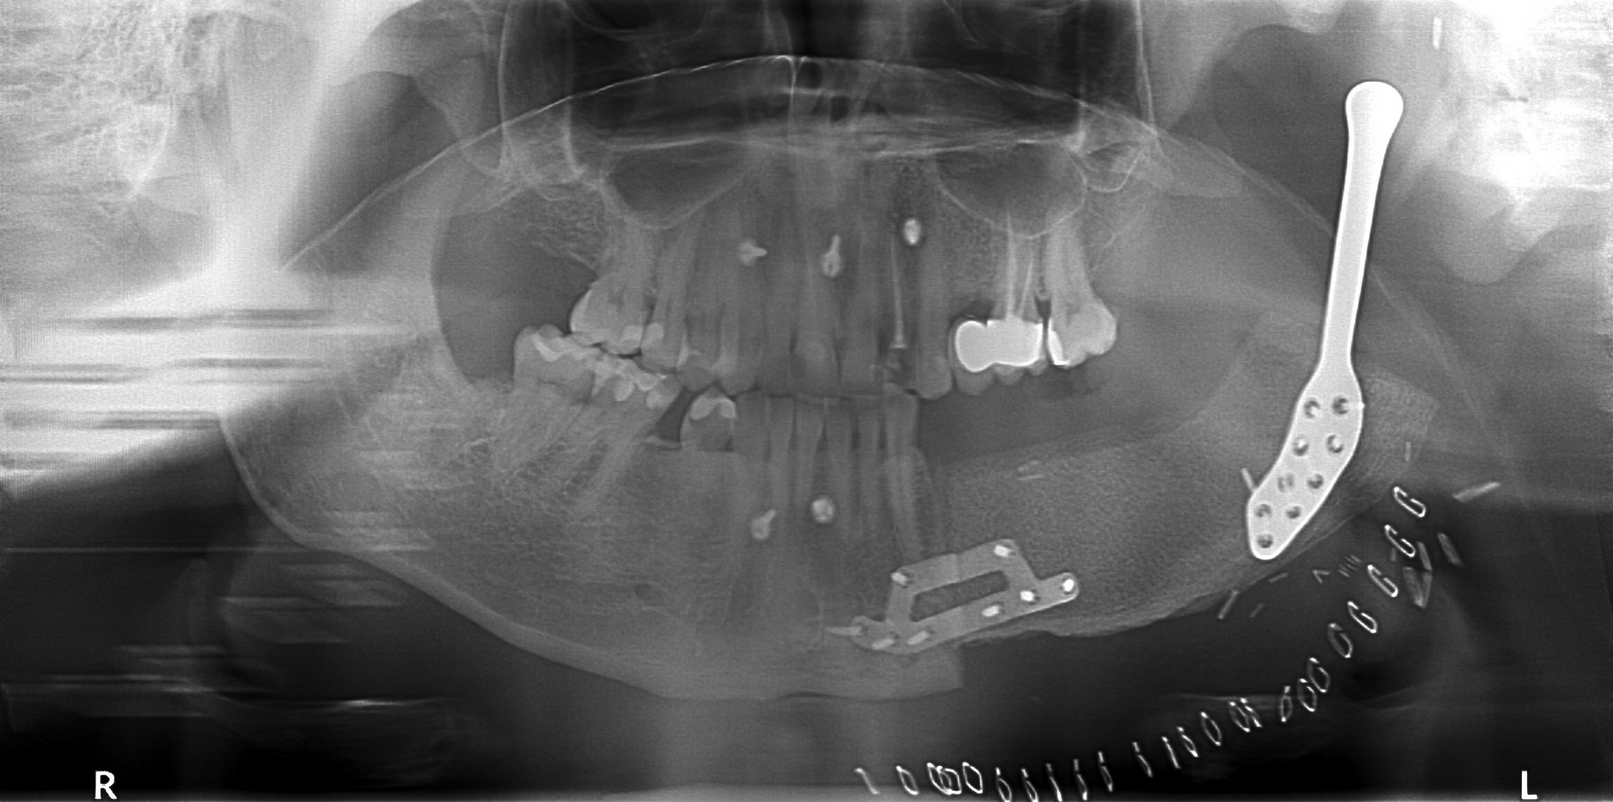

Jednym z najbardziej skomplikowanych zabiegów z przeprowadzonych w Klinice była rekonstrukcja stawu skroniowo-żuchwowego z wykorzystaniem materiału alloplastycznego, wykonanego w technologii druku 3D. W tym przypadku dodatkowo zastosowano płat biodrowy kostno-mięśniowy, pobrany za pomocą szablonu przygotowanego indywidualnie dla pacjenta. To rozwiązanie otwiera nowe możliwości leczenia pacjentów z nowotworami w obrębie części twarzowej czaszki, znacząco poprawiając ich jakość życia.